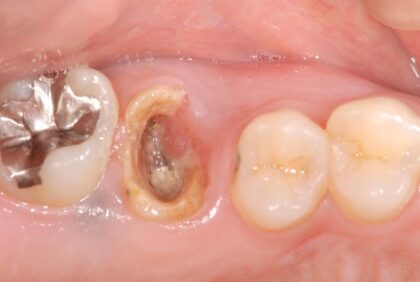

移植前

重度虫歯の右上6番の歯に、右上の親知らず(8番目)を移植しました。

移植後